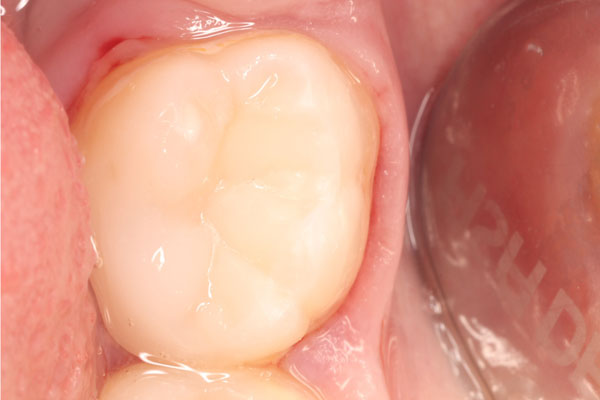

Лечение под микроскопом: фото До и После